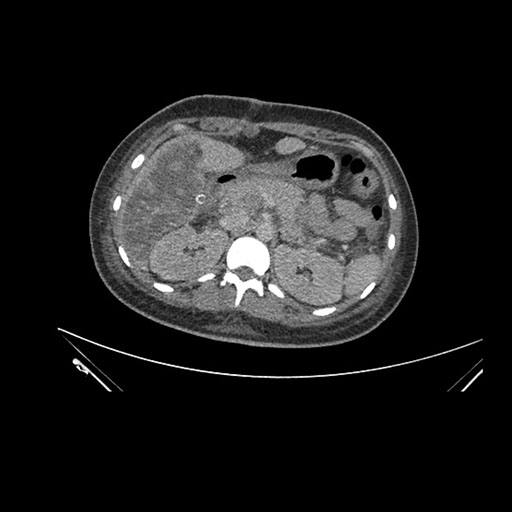

Axial Arterial

Axial Venous

Coronal Arterial

Coronal Venous

Imaging analysis

Based on initial findings, which issue(s) would you be most concerned about?